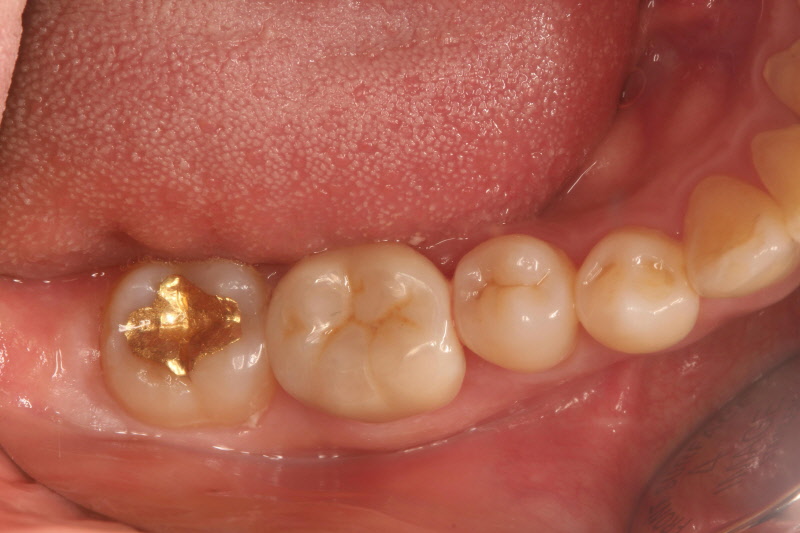

3) 금

아말감과 함께 오랜 시간 사용되어 온 재료이며 여러 재료 중 재료 자체의 안정성과 수명에 있어 제일 나은 재료입니다. 금의 좋은 점은 충전물 자체의 파절이 없다는 것입니다. 주위 잔존 치아의 파절 문제나 2차 충치로 인한 수명은 문제가 될 수 있겠지만 매워 놓은 금 재료 자체가 문제가 되는 경우는 별로 없습니다.

사용되는 금은 순수한 금을 사용할 수 없습니다. 순수한 금은 너무 물러 씹는 힘에 대해 저항하거나 형태를 유지하기 힘들기 때문입니다. 하여 치과용으로 합금의 형태를 만들어 사용하는 것이 일반적입니다. 여러 가지 금속을 추가하여 치과용으로 쓰기 좋게 만드는 것이지요. 금의 함량은 많으면 3/4정도까지도 됩니다. 금이 많으면 좀더 정밀하게 만들 수 있고 적합성이 좋아지지만 경도, 강도에서 감소하게 되어 각각의 충치 경우에 맞는 금을 사용하는 것이 최선이 됩니다.

이처럼 금의 장점이 충전물 자체의 강도가 좋다는 점이므로 조금 힘을 받는 부위에 사용할 수 있습니다. 조금 큰 우식이나 치아와 치아 사이의 충치에서는 금으로 충전하는 것이 가장 믿음직합니다. 단점으로는 금의 유지를 위해 치과용 시멘트를 사용하게 되는데 이 시멘트가 시간이 지나면서 녹아서 없어져서 금 수복물이 탈락하거나 2차 충치의 발생 원인이 될 수 있습니다. 금의 유지를 위해 치아를 일정한 형태대로 삭제하여야 하여 다른 재료보다 치아 삭제가 좀더 많은 것도 단점입니다. 비용이 다소 비싼 치료 방식이며, 1회에 마무리되지 않고 2회에 걸쳐 치료가 되어야 합니다. 여러 단계를 거쳐 치료를 마무리하게 되므로 각각의 단계를 정확하게 해야만 좋은 재료의 장점을 최상으로 만들 수 있을 것입니다.